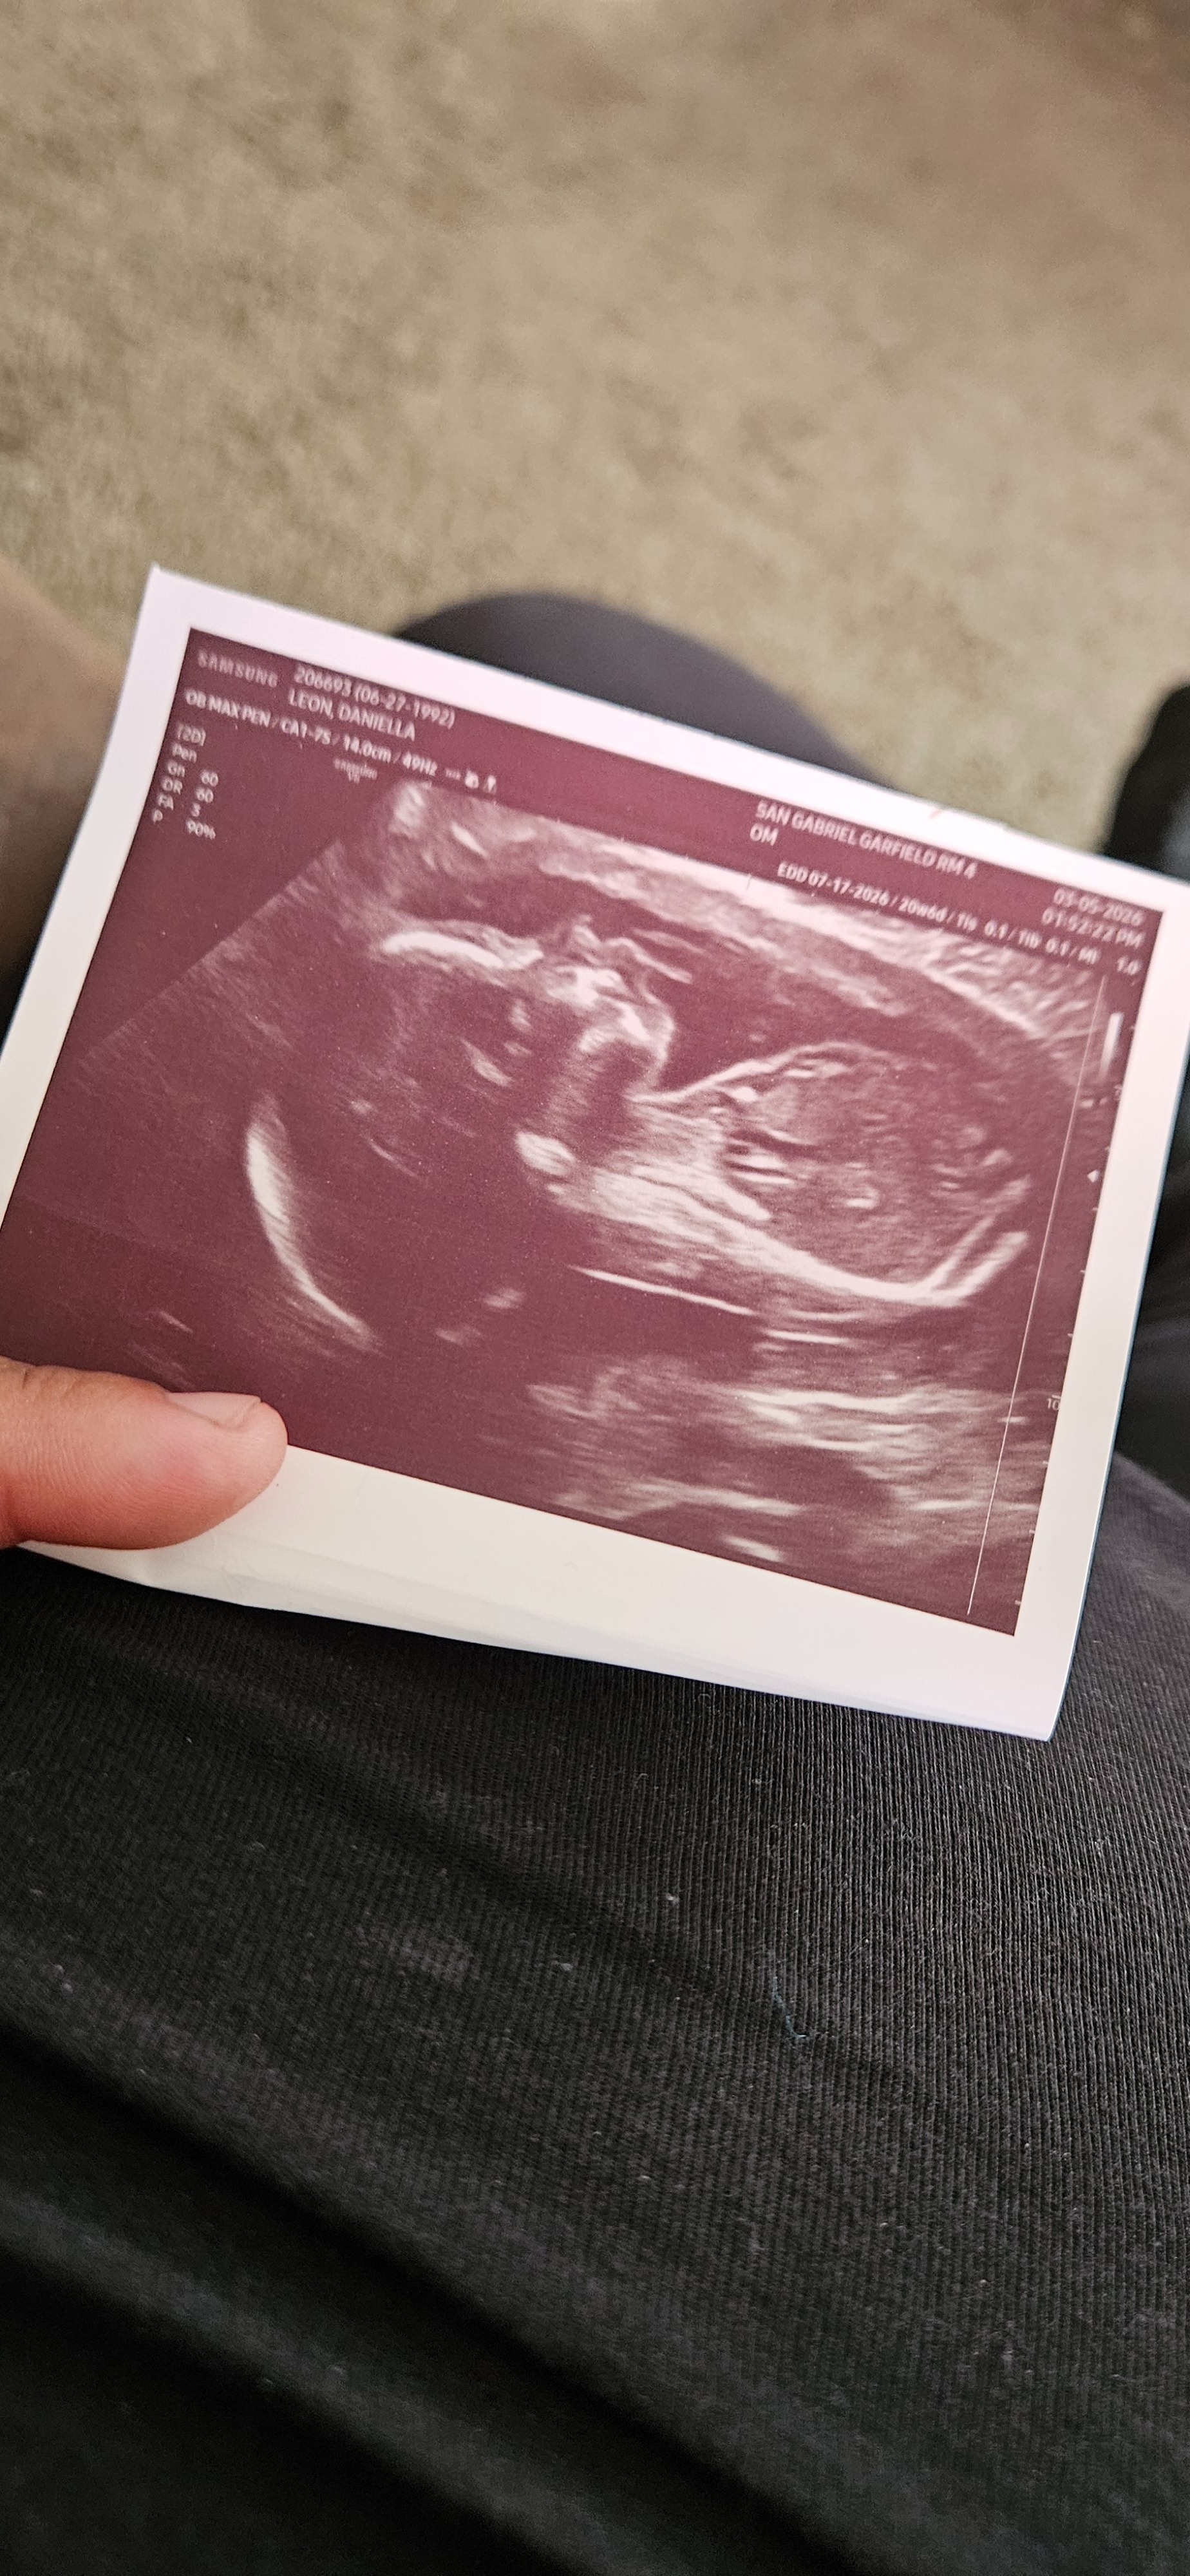

Hello, everyone. My name is Lala. My husband's name is Brian. Unfortunately, I had to come here and ask for help from family members, friends, and anybody who maybe has gone through this and knows how tough it can be. But just at twenty-two weeks and four days, on Monday night, my water broke and I went into labor. I delivered my baby boy, Brian Jr., on March 17th. Tragically, he was only able to spend eleven minutes with us before passing away in his father's arms. The overwhelming loss of our baby boy has brought unimaginable pain and grief, and Brian and I are left to lean on one another as we try to navigate this overwhelming loss.